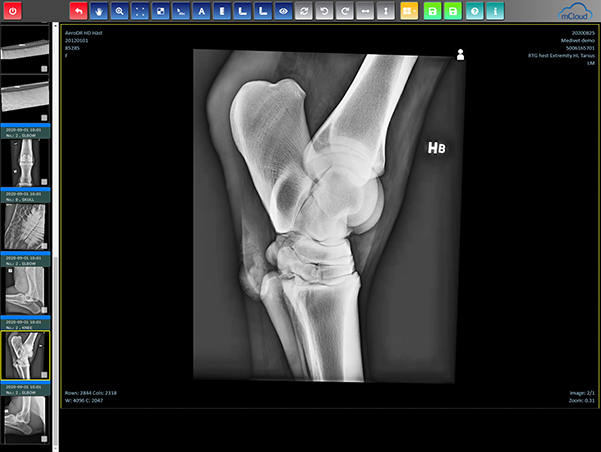

Det betyder att bilderna/filerna följer medicinsk standard för radiologiska bilder. DICOM WG25 filer innehåller dels en högupplöslig JPEG bild men även datainformation om när bilden är tagen, anatomi och projektion, vad djuret heter, dess ID och ägarens efternamn.

Det gör DICOM till ett säkrare format och minskar risken för förfalskning eller lurendrejerier. Förutsatt att er digitala utrustning kan generera DICOM bilder så kan ni även ladda upp dem i mcloud. Det gäller alla modaliteter som CR, DR, Ultraljud, MR, CT, PACS, Endoskopi etc, egentligen alla apparaten som producerar medicinska bilder.

mcloud har även en smart funktion där all DICOM informationen i bilden enkelt kan visas genom ett knapptryck.

Känner ni igen svårigheten med att diskutera bilder på distans? Olika system, strul med att ladda bilder från olika lagringsmedier, olika inställningar, eller vad det nu är som försvårar. Med mcloud kan både sändaren som mottagaren titta på bilderna på samma sätt. Tänk att ni bägge har bilderna uppe i varsin mcloud och går igenom dem t.ex. per telefon. En bild säger mer än tusen ord, och ifall man kan se dem så samma vis blir det enklast möjligast att kommunicera.